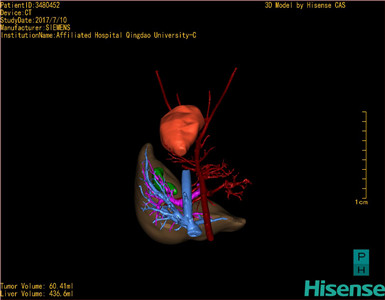

通过调节窗宽窗位调整CT序号,对肿瘤,肝实质,胆囊,下腔静脉,肿瘤,肝动脉、门静脉及肝静脉等进行三维重建;系统自动计算肿瘤体积和肝脏体积。模拟手术操作,自动计算切除肿瘤体积。肝脏体积为436.6ml,肿瘤体积为60.41ml,与血管联系紧密,术前手术方案的规划。

术前三维重建:

重建图片